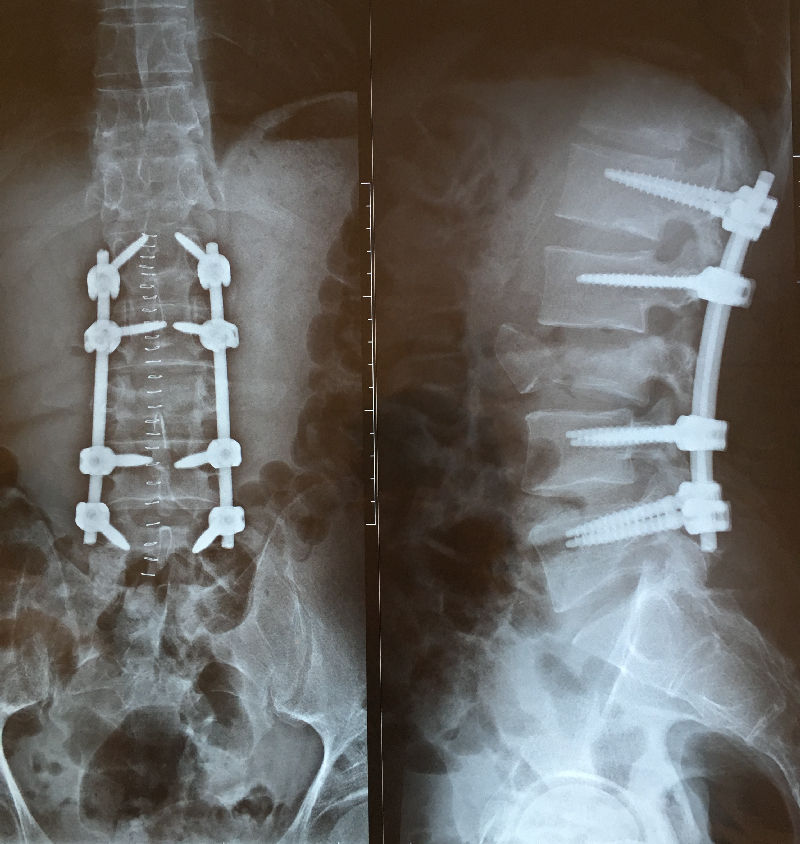

Рентгеновские снимки и медицинские изображения компрессионных переломов